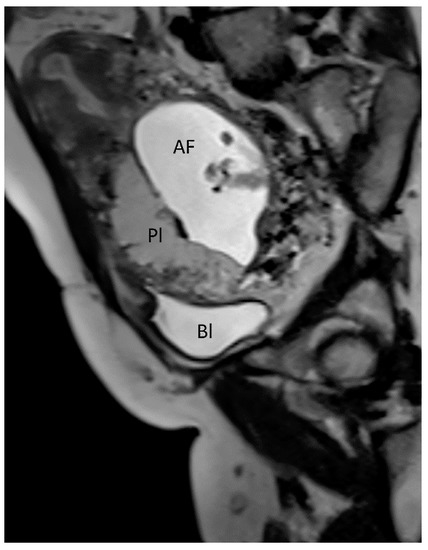

3.1.1. Placenta Accreta Spectrum